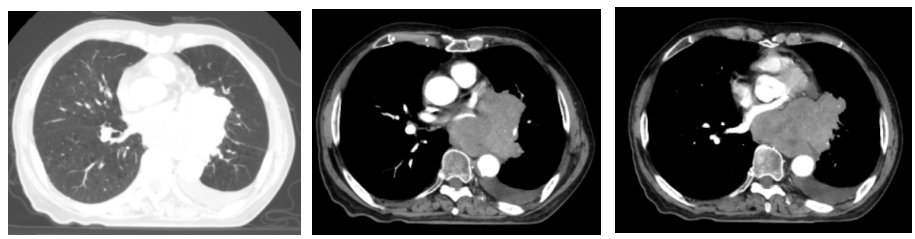

2022-07-19(2周期后)胸部、全腹部增强CT:1.肺癌复查,较前(2022-05-23)左肺门占位明显减小,左肺下叶远端阻塞性改变较前范围减小;2.双肺肺气肿;3.左侧胸腔积液,累及左侧胸膜可能,较前略增多;4.心包少量积液,较前增多;5.肝内多发囊肿;右肾上极小囊肿;6.肝左叶内小海绵状血管瘤可能;7.前列腺增大伴钙化。

2022-09-30(4周期后)胸部、全腹部增强CT:1.肺癌复查,较前(2022-07-19)左肺门占位减小,左肺下叶远端阻塞性改变较前范围减小;2.双肺肺气肿;3.左侧胸腔积液,累及左侧胸膜可能,较前减少;4.心包少量积液,大致同前;5.肝内多发囊肿;右肾上级小囊肿;6.肝左叶内小海绵状血管瘤可能;7.前列腺增大伴钙化。

2022-11-21(6周期后)胸部、全腹部增强CT:左肺门占位较前(2022-09-30)减小,左肺下叶远端阻塞性改变较前变化不大;左侧胸腔积液,累及左侧胸膜可能,较前减少;心包少量积液,大致同前。

疗效评估:PR(接近CR)。